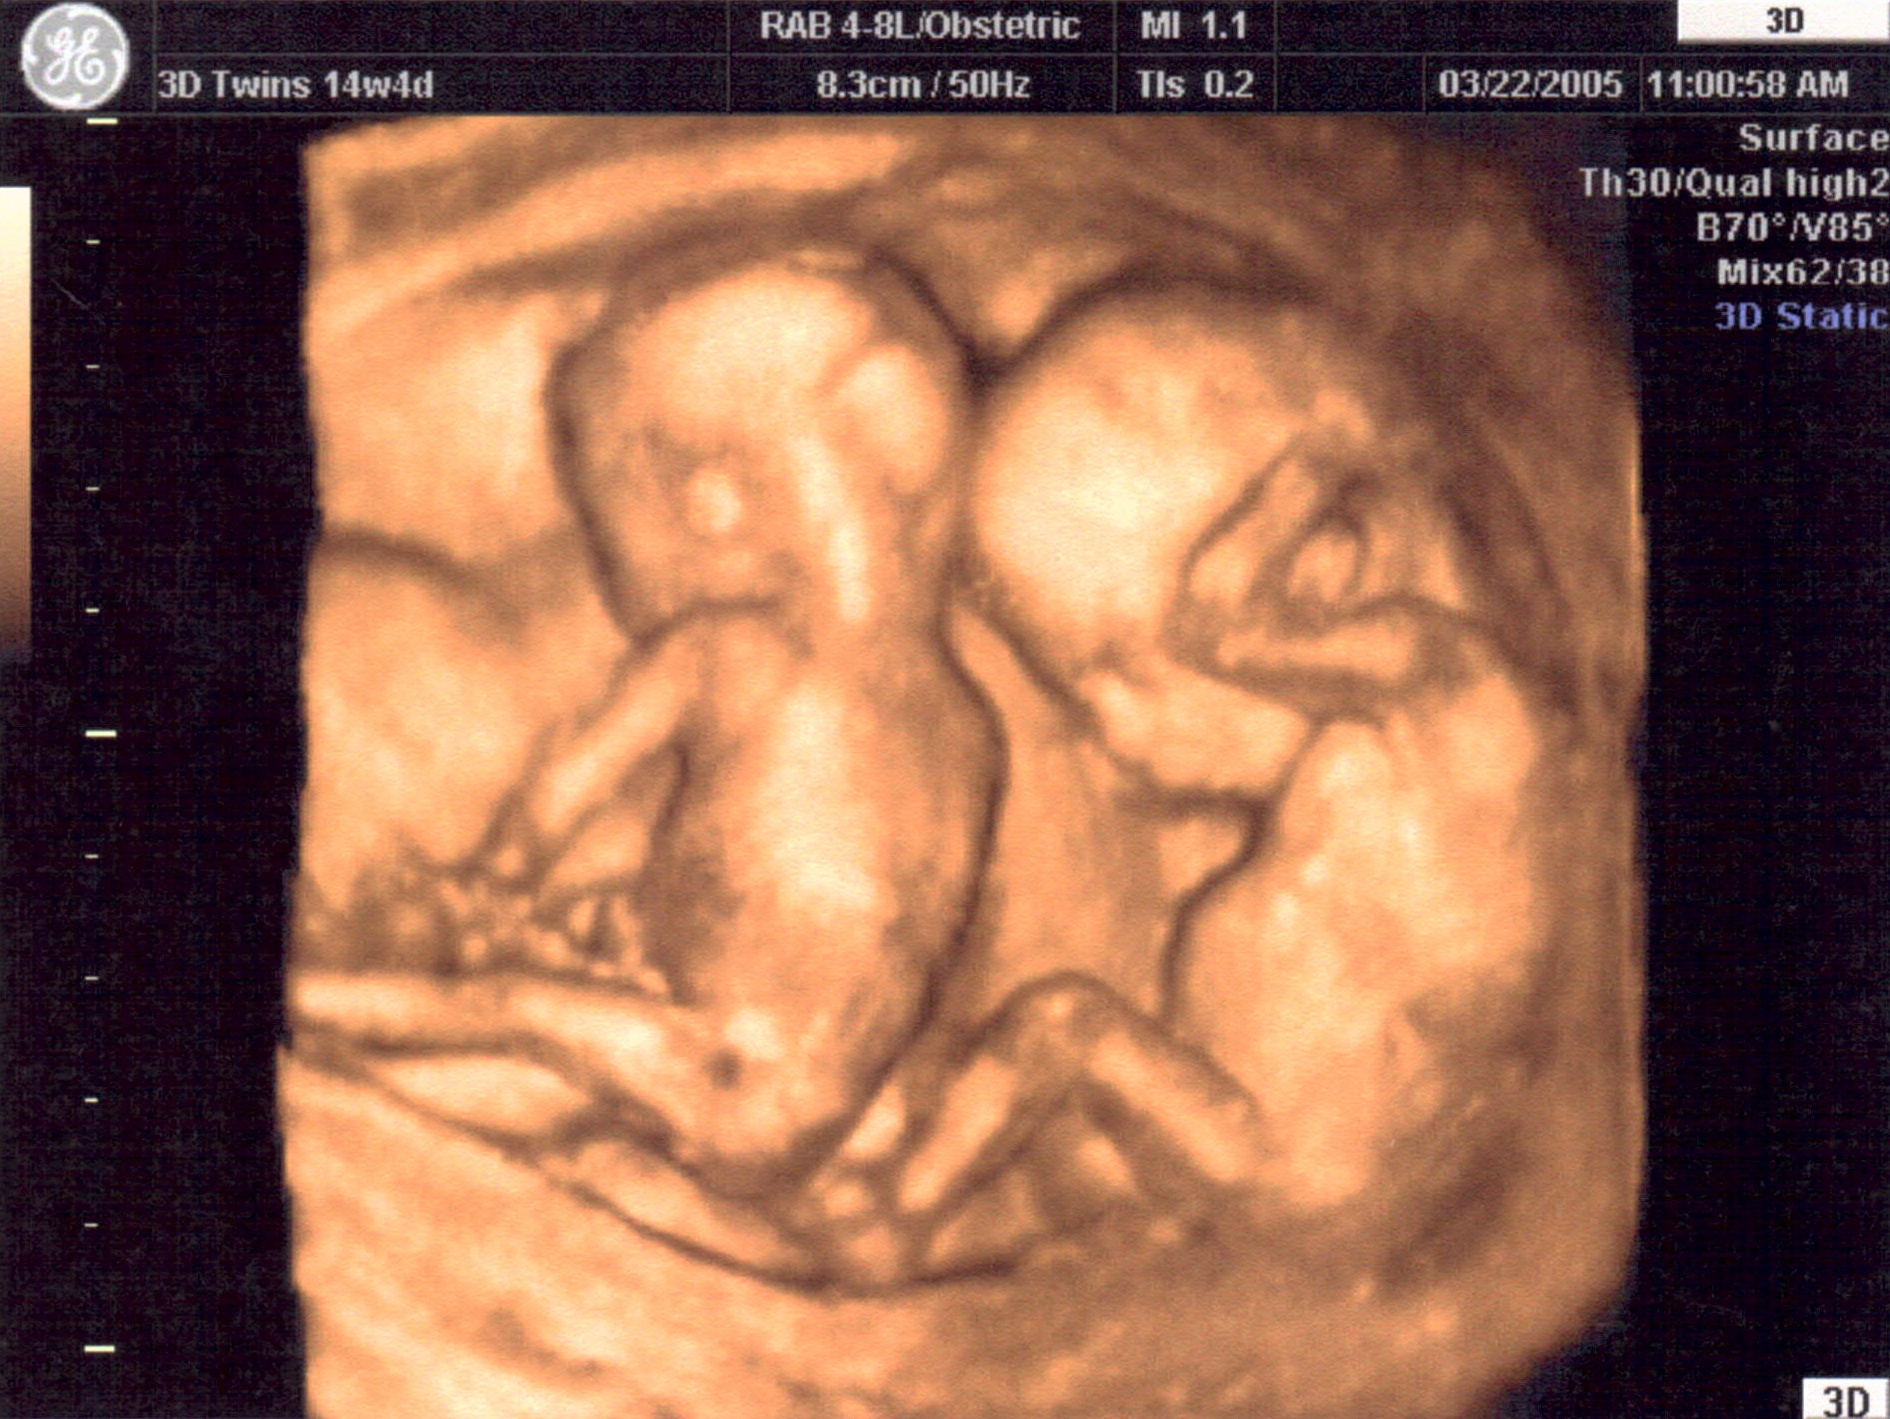

Gallery ECO